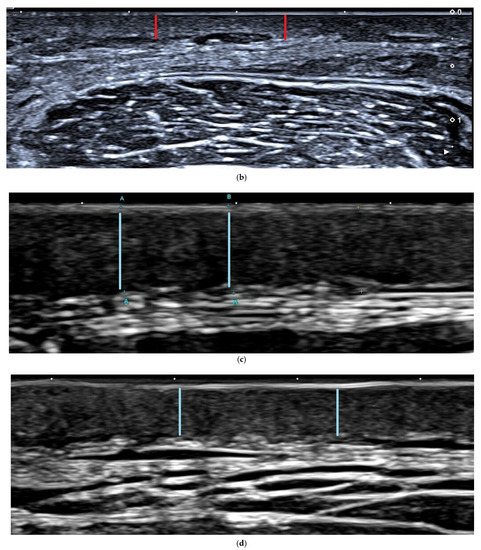

Figure 3.

Ultrasonic images of patients four weeks before and after treatment. (a) AFL+MTX group patient 4 weeks before treatment. The uppermost layer, the epidermis layer, is hyperechoic (shown with white arrows), and the underlying dermis is hypoechoic (shown with red line) and indistinguishable from the fat layer. (b) AFL+MTX group patient 4 weeks after treatment. The dermis is thinner than before (shown with red line) and can be easily distinguished from the fat layer. (c) AFL group patient 4 weeks before treatment. The dermis (shown with blue line) is indistinguishable from the fat layer. (d) AFL group patient 4 weeks after treatment. The dermis is thinner (shown with blue line) than before and clearly identified with the fat layer.